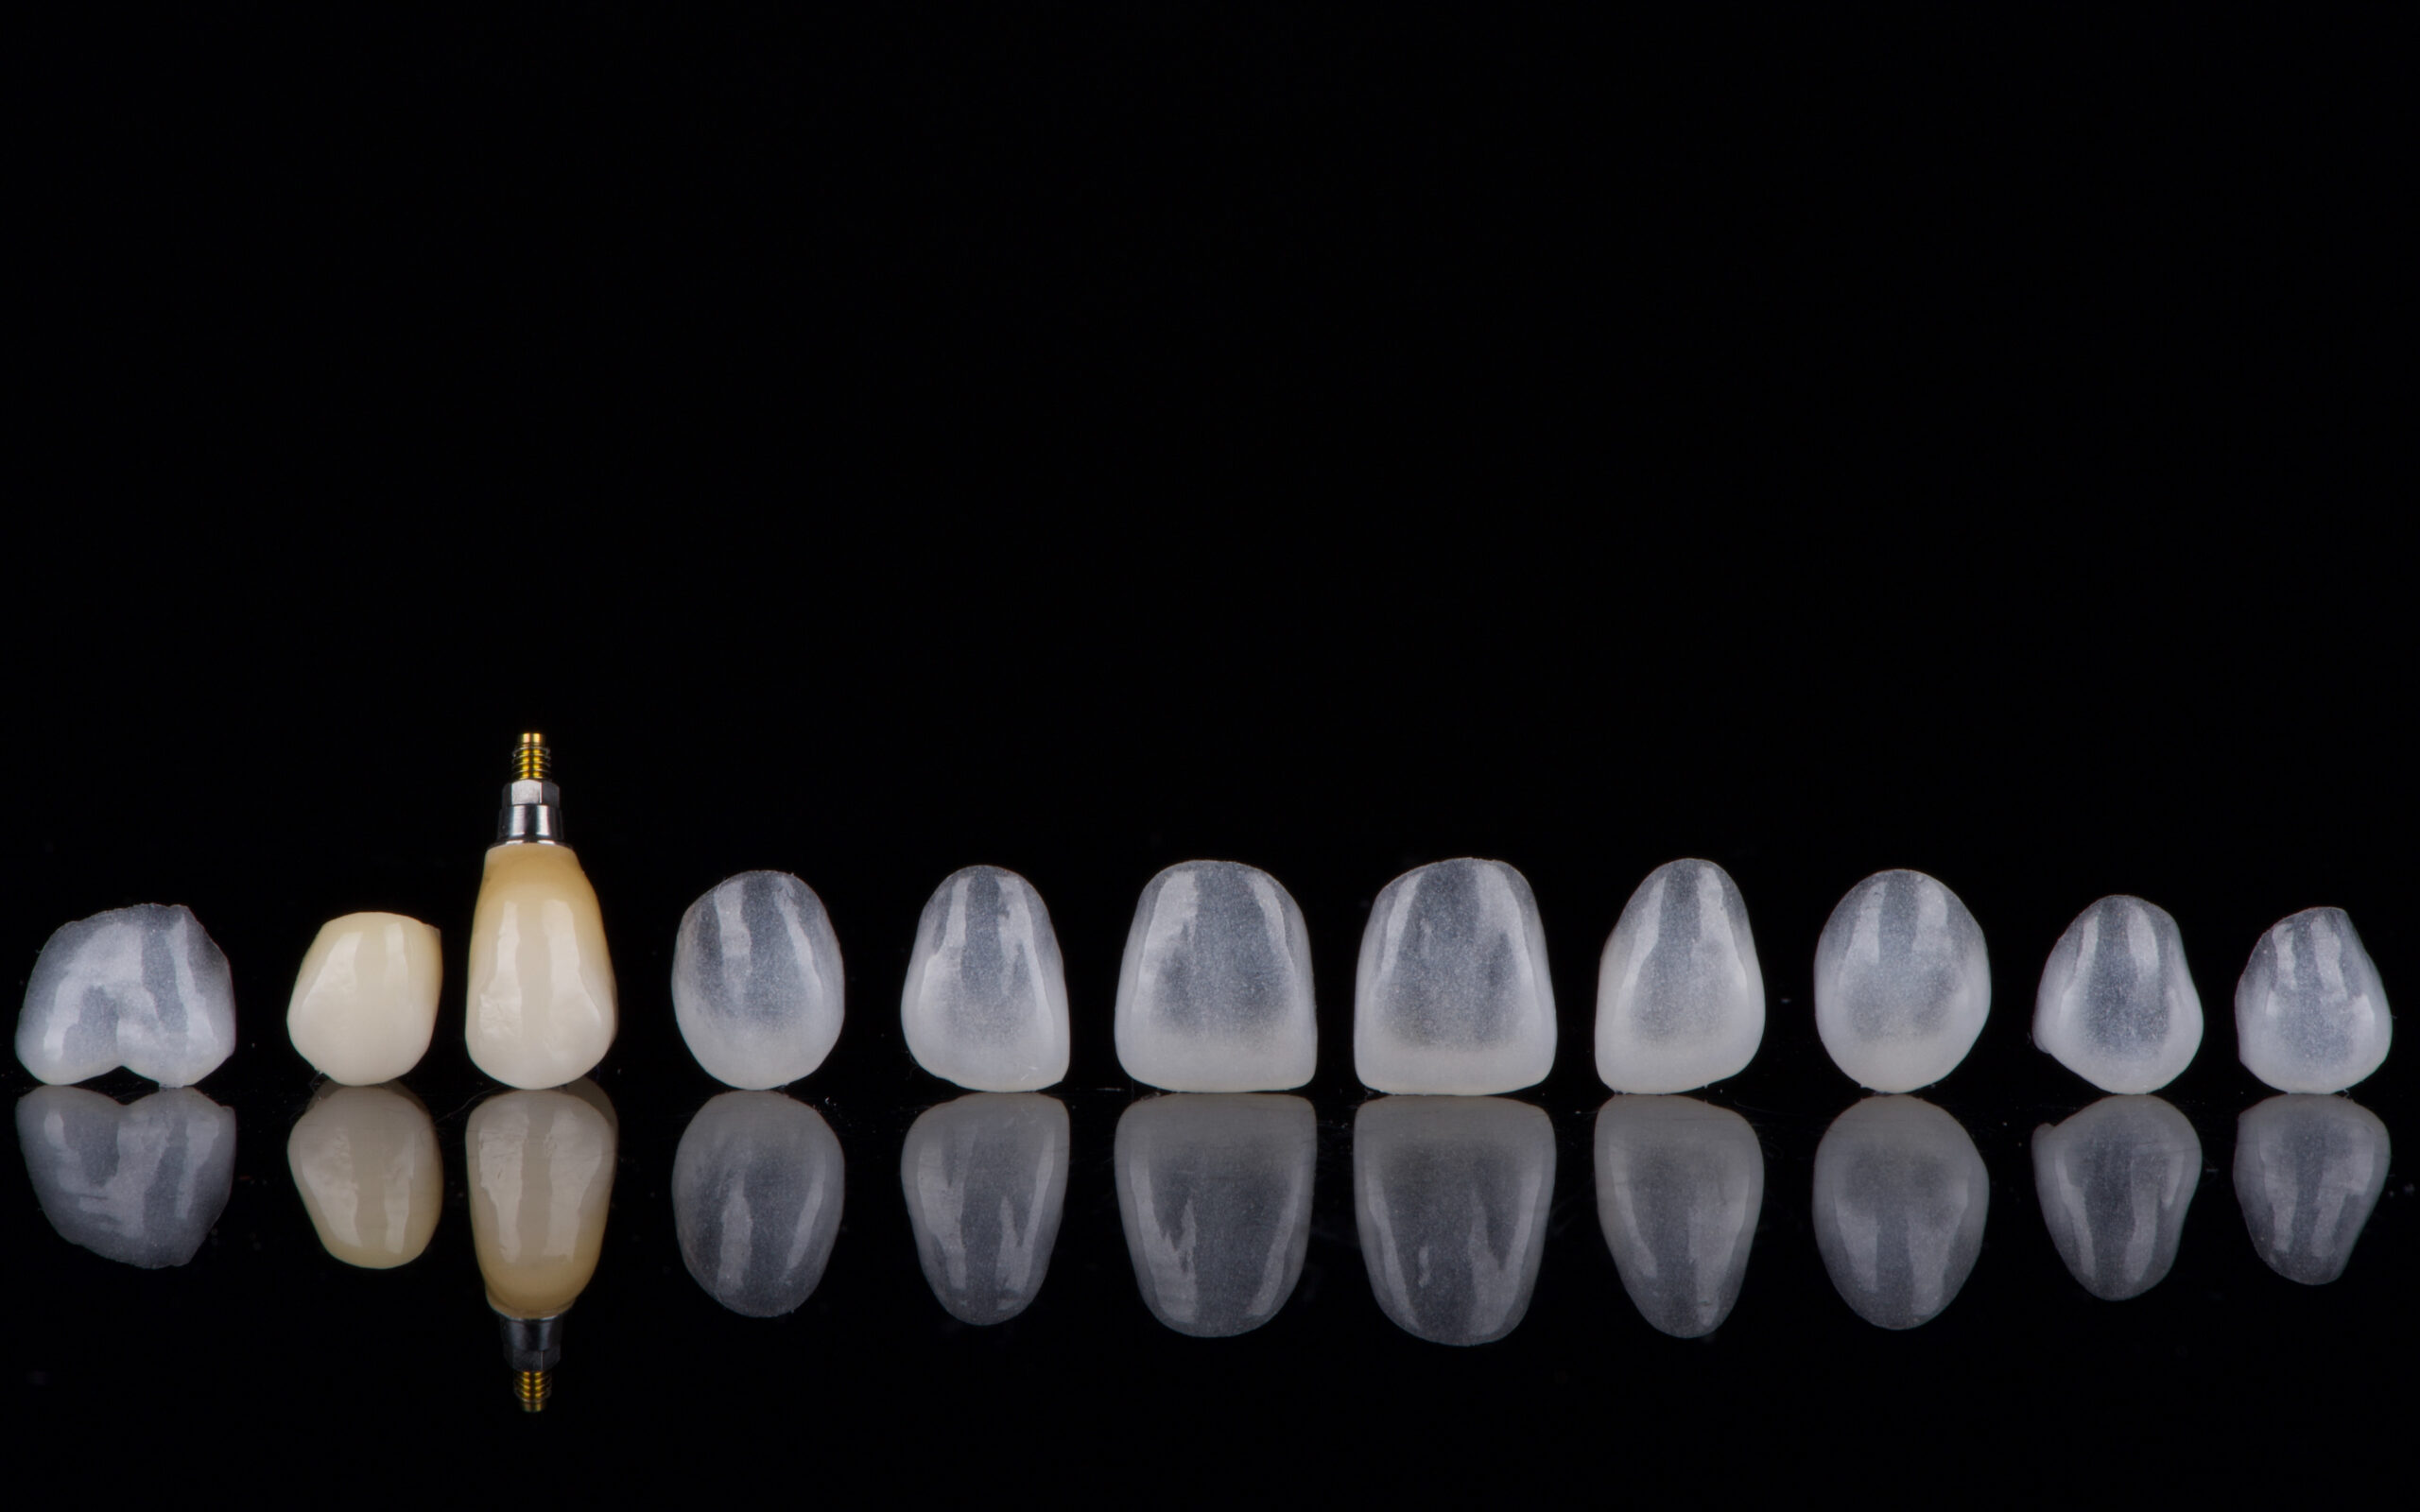

Klinikinis atvėjis TEST